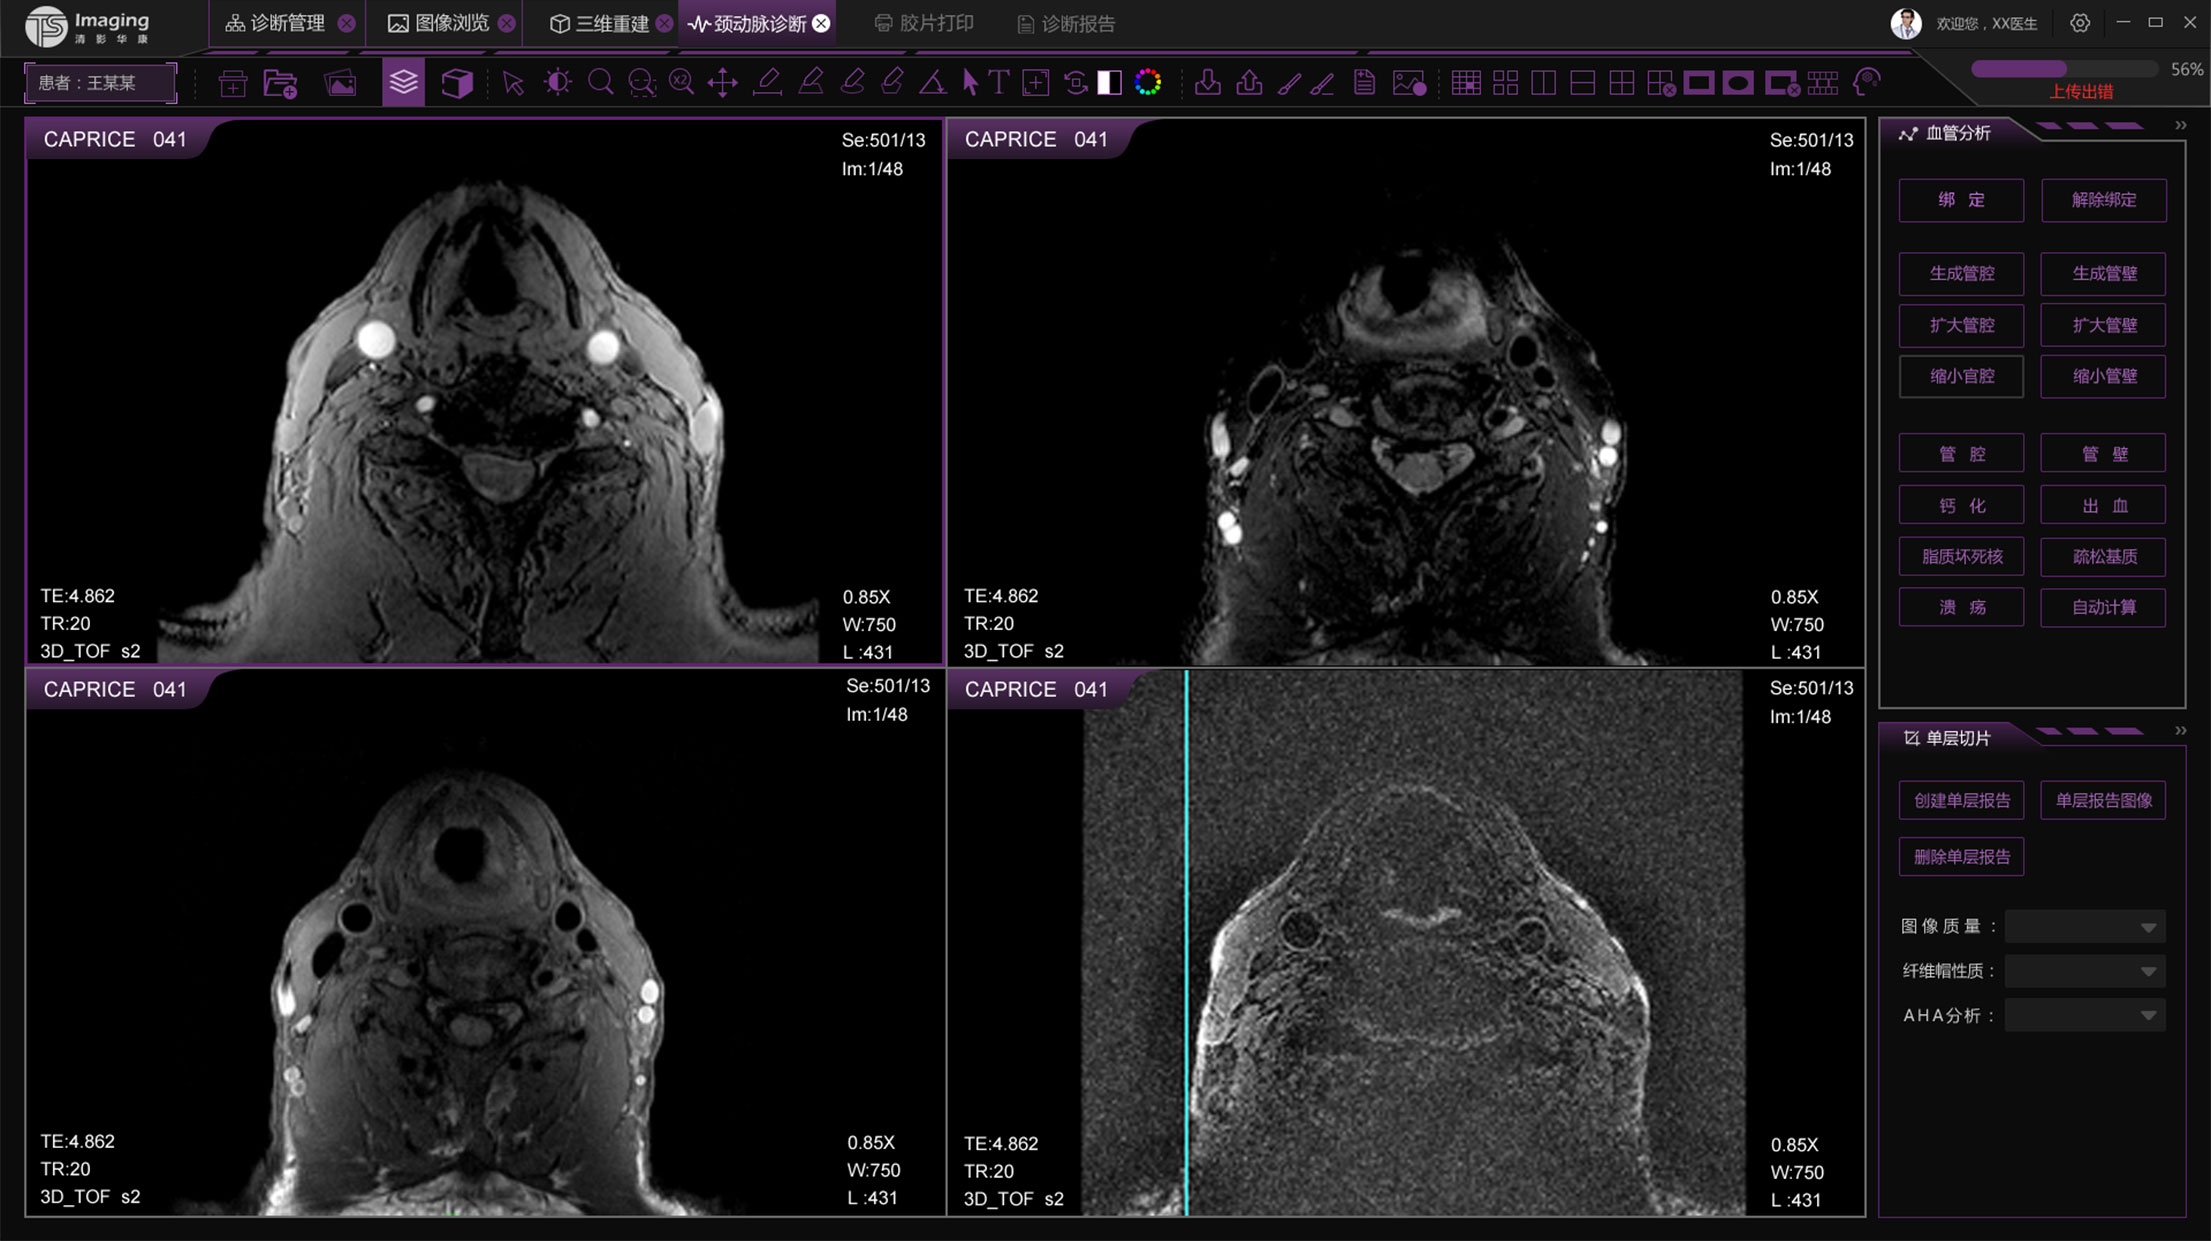

頸動脈診斷頁面

頸動脈診斷頁面整體布局和三維重建比較相似,最大的區別是右側的操作區域,血管分析都為按鍵操作,通過間隔的大小分成三部分。單層切片除了按鍵還有下拉菜單的操作。